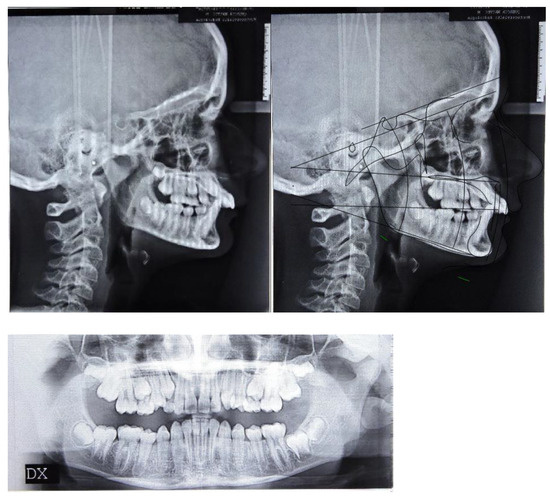

At clinical examination, dental Class I and crowding correction, with proper incisor inclination, and ideal overjet and overbite were achieved (Figure 4).

Figure 4.

Post-treatment intraoral, extraoral photographs and radiographic examination.

Follow-up orthopantomography showed good root parallelism, without any sign of crestal bone loss and apical root resorption; however, a supernumerary maxillary right tooth was noticed (Figure 4).

Post-treatment lateral teleradiograph showed skeletal, dental and aesthetic improvements (Table 1 and Figure 4)

- Skeletal outcomes: cephalometric analysis according to Bjork showed a skeletal Class I relationship (ANB = 2°, Wits = 3 mm). Referring to the anterior cranial base (SN plane: Sella-Nasion), the patient presented a properly sagittal (SNB = 81°) and vertical position of the mandible with an increase in the angle (FMA) between the mandibular plane (ML) and Frankfort’s plane (FH) at the end of treatment (FMA = 21°)

- Dental outcomes: the cephalometric analysis according to Down revealed a change in the inclination of the occlusal plane referring to Frankfort’s plane (OP-FH = 5°), whereas the angle between the maxilla (palatal plane, ANS/PNS) and the Frankfort’s plane was unchanged at the end of treatment (ANS/PNS-FH = 4°). The inclination of the upper incisors was reduced at the end of treatment (Sup/SN = 112°) along with a flat curve of Spee and proper overjet (OJ = 5 mm) and overbite (OB = 4 mm). The inclination of the mandibular incisors remained the same at the end of treatment (IMPA = 90°).

- Aesthetic outcomes: the soft tissue changes involved a straight profile with the jaws proportionately positioned in the sagittal plane. On a frontal view the patient showed an increase in anterior vertical dimension along with an ideal smile arc. From a functional point of view, the lip interposition between the upper and mandibular incisors was corrected (Figure 4 and Figure 5).